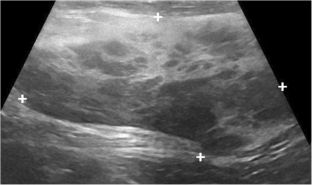

Breast tissue undergoes a series of changes from birth to puberty. The majority of the changes are transient, related to physiological hormonal changes. Although the breast is identical in both sexes at birth, its histology and development will eventually differ. It is important for radiologists to have a basic understanding of endocrinological changes and appearance on imaging to avoid potential pitfalls, particularly on ultrasound, which is the primary modality used to evaluate the breast.